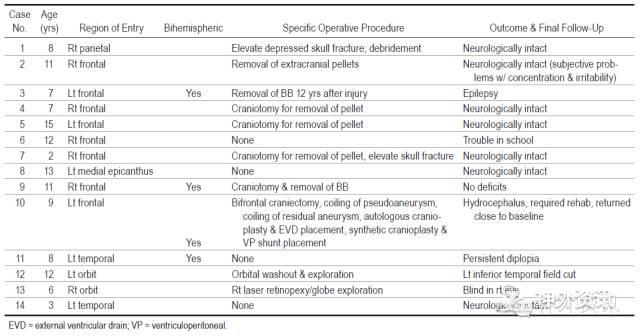

57%患儿是额部受到枪击,引起外伤性蛛网膜下腔出血(50%)、颅骨凹陷性骨折(29%)、脑挫裂伤(29%)、脑出血(7%)、脑室内出血(7%)和假性动脉瘤形成(7%)。患儿均无死亡。10例(71%)施行外科手术,包括取出颅内枪弹、伤道探查或清创、凹陷性骨折整复和脑脊液分流术等(表1、图1)。

表1. 14例患儿年龄、枪击部位、手术和预后情况。